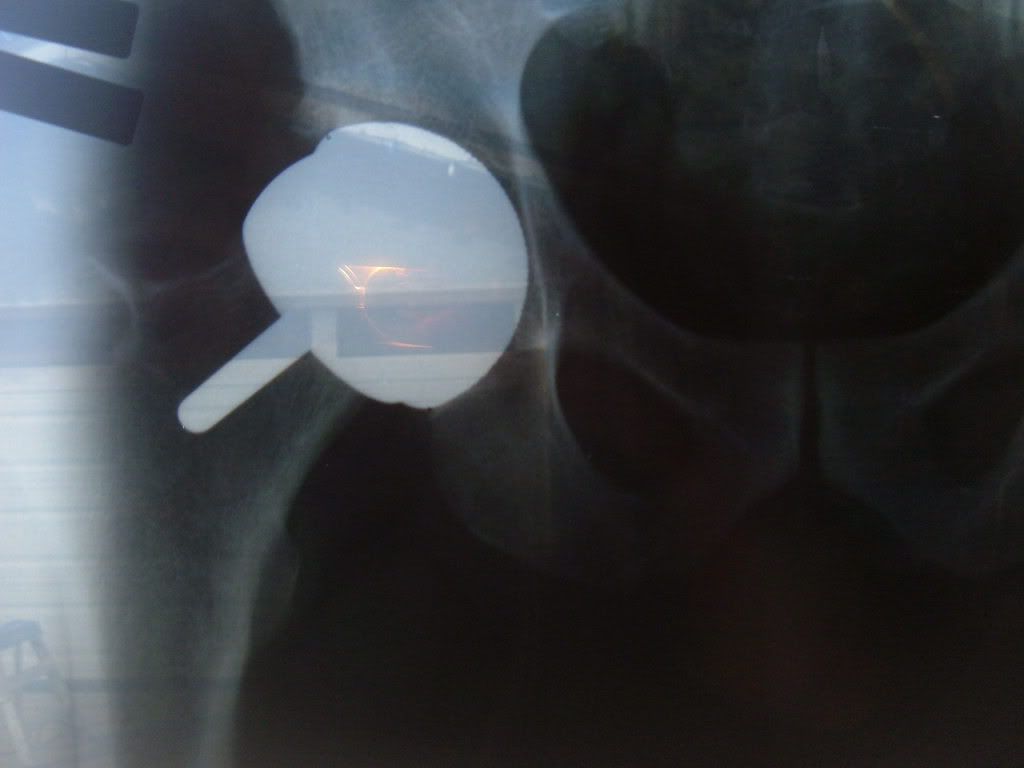

OK here are the x-rays. They didn't have them on a disc so I hung them no the slider and took pics so the quality aint that great but you can get an idea of why I'm concerned.

:o ::)   Kinda looks more like the bad examples than the good examples huh ?    I feel like I wanted my body to run like a Ferrari but somehow wound up with Hyundai mechanic..... ::)   I had about 20 questions for the doctor, his opinion is a revision has too many downsides and to just move on and "Keep an eye on it".  But don't know what to keep an eye on because he says Kaiser does not have any good tests for metal ions, but they are working on subbing them out to an outside independent testing lab.  A cup revision is only possible if he used the thinner of the 2 cups available, at the time of our meeting he did not know wich thickness he put in........(no comment  ::)  There is no reason to even think about a revision until I find out wich cup was used.  The good news is that it's starting to work better and better so I am encouraged there !!   I am going to get a couple other opinions but am finally feeling like it's going to be ok and my life is getting back to normal.  I will keep you posted, Thanks again for all your concern, Bill.

Thanks for posting the x-rays.  One positive sign - the joint looks better for the cross table lateral view, when the hip is abducted.  That means you are better aligned for bull riding, bronco busting or motocross (if you have a wide motocycle seat)  :).